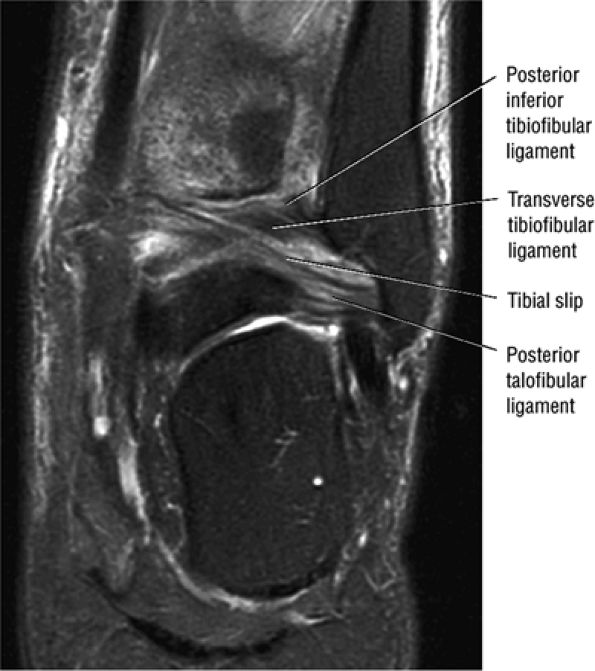

The syndesmotic ligaments consist of the anterior syndesmotic or anterior inferior tibiofibular ligament and the posterior syndesmotic or posterior inferior tibiofibular ligament, the interosseous membrane, and the transverse tibiofibular ligament.

The transverse tibiofibular ligament represents the posterior labrum of the ankle and projects inferior to the posterior tibial margin.

The tibial slip is the posterior intermalleolar ligament.